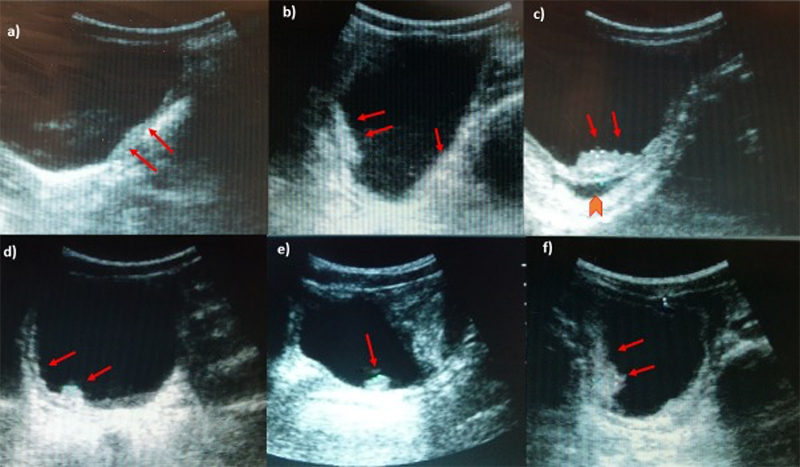

- Periportal fibrosis – thickening of the hyperechoic borders of the portal vein and branches.

Figure 54A. Transverse views of the liver revealing moderate periportal fibrosis. Note the thickened hyperechoic walls surrounding the portal vein and branches.

Figure 54B. Transverse views of the liver revealing moderate periportal fibrosis. Note the thickened hyperechoic walls surrounding the portal vein and branches.